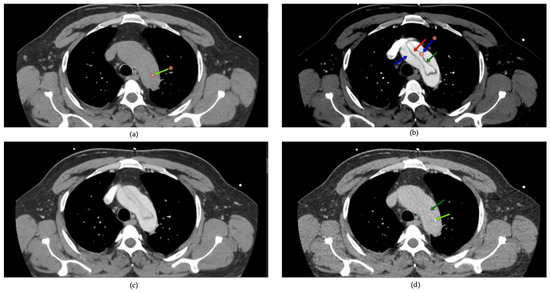

All patients received TTE upon admission. The assessment was conducted on left ventricular ejection fraction (LVEF), the presence of pericardial effusion, and wall motion abnormalities. The dimensions of the aorta and the presence of aortic valve pathology were recorded. CTA was conducted on all patients to verify the diagnosis of dissection, determine the extent of dissection (including the ascending aorta, aortic arch, and descending aorta), and assess for complications such as periaortic hematoma, rupture, or involvement of visceral arteries. Scans utilized a 128-slice CT scanner with contrast enhancement to delineate both true and false lumens. One of the critical aspects of evaluating aortic pathologies is the accurate visualization of the aortic lumen and wall structures through CT imaging. However, non-gated CT scans are susceptible to pulsation artifacts, which can obscure essential details and lead to diagnostic challenges. Common pulsation artifacts observed in this study are illustrated in Figure 2.

Figure 2. Artifacts in non-gated computed tomography: pulsation effects in aortic imaging: common artifacts from pulsation in non-gated computed tomography (CT) imaging are highlighted with green arrows (b,c). These artifacts can obscure critical details of the aortic wall and luminal structure, potentially complicating the assessment of aortic dissections (a,d). Accurate interpretation requires recognizing and mitigating such limitations.